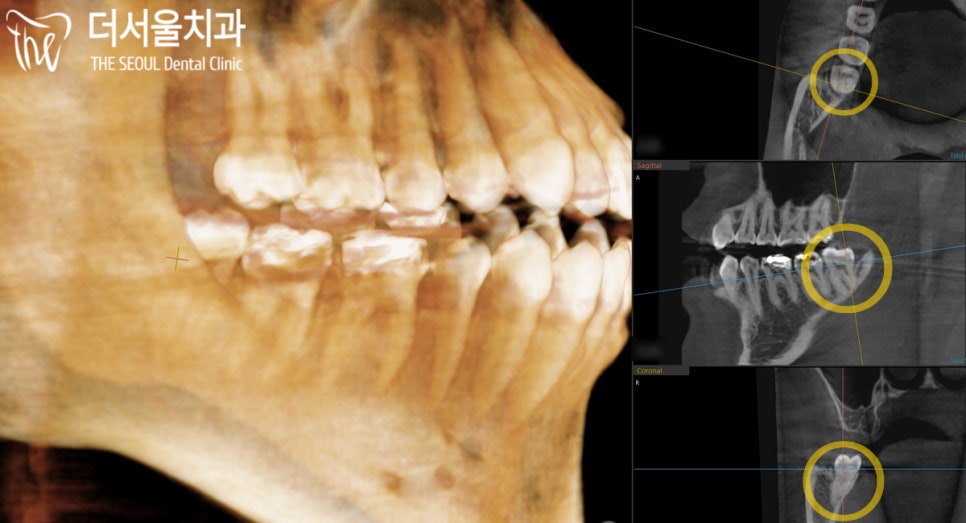

파노라마 상에서는 신경관과 치아의 뿌리가

굉장히 근접해있는 것으로 확인되었습니다.

CT 촬영을 통해 좀 더 자세히 살펴본 결과,

충분한 거리가 주어진 것은 아니었지만

이 정도면 안전하게 뽑을 수 있을 거란 판단이 들었습니다.